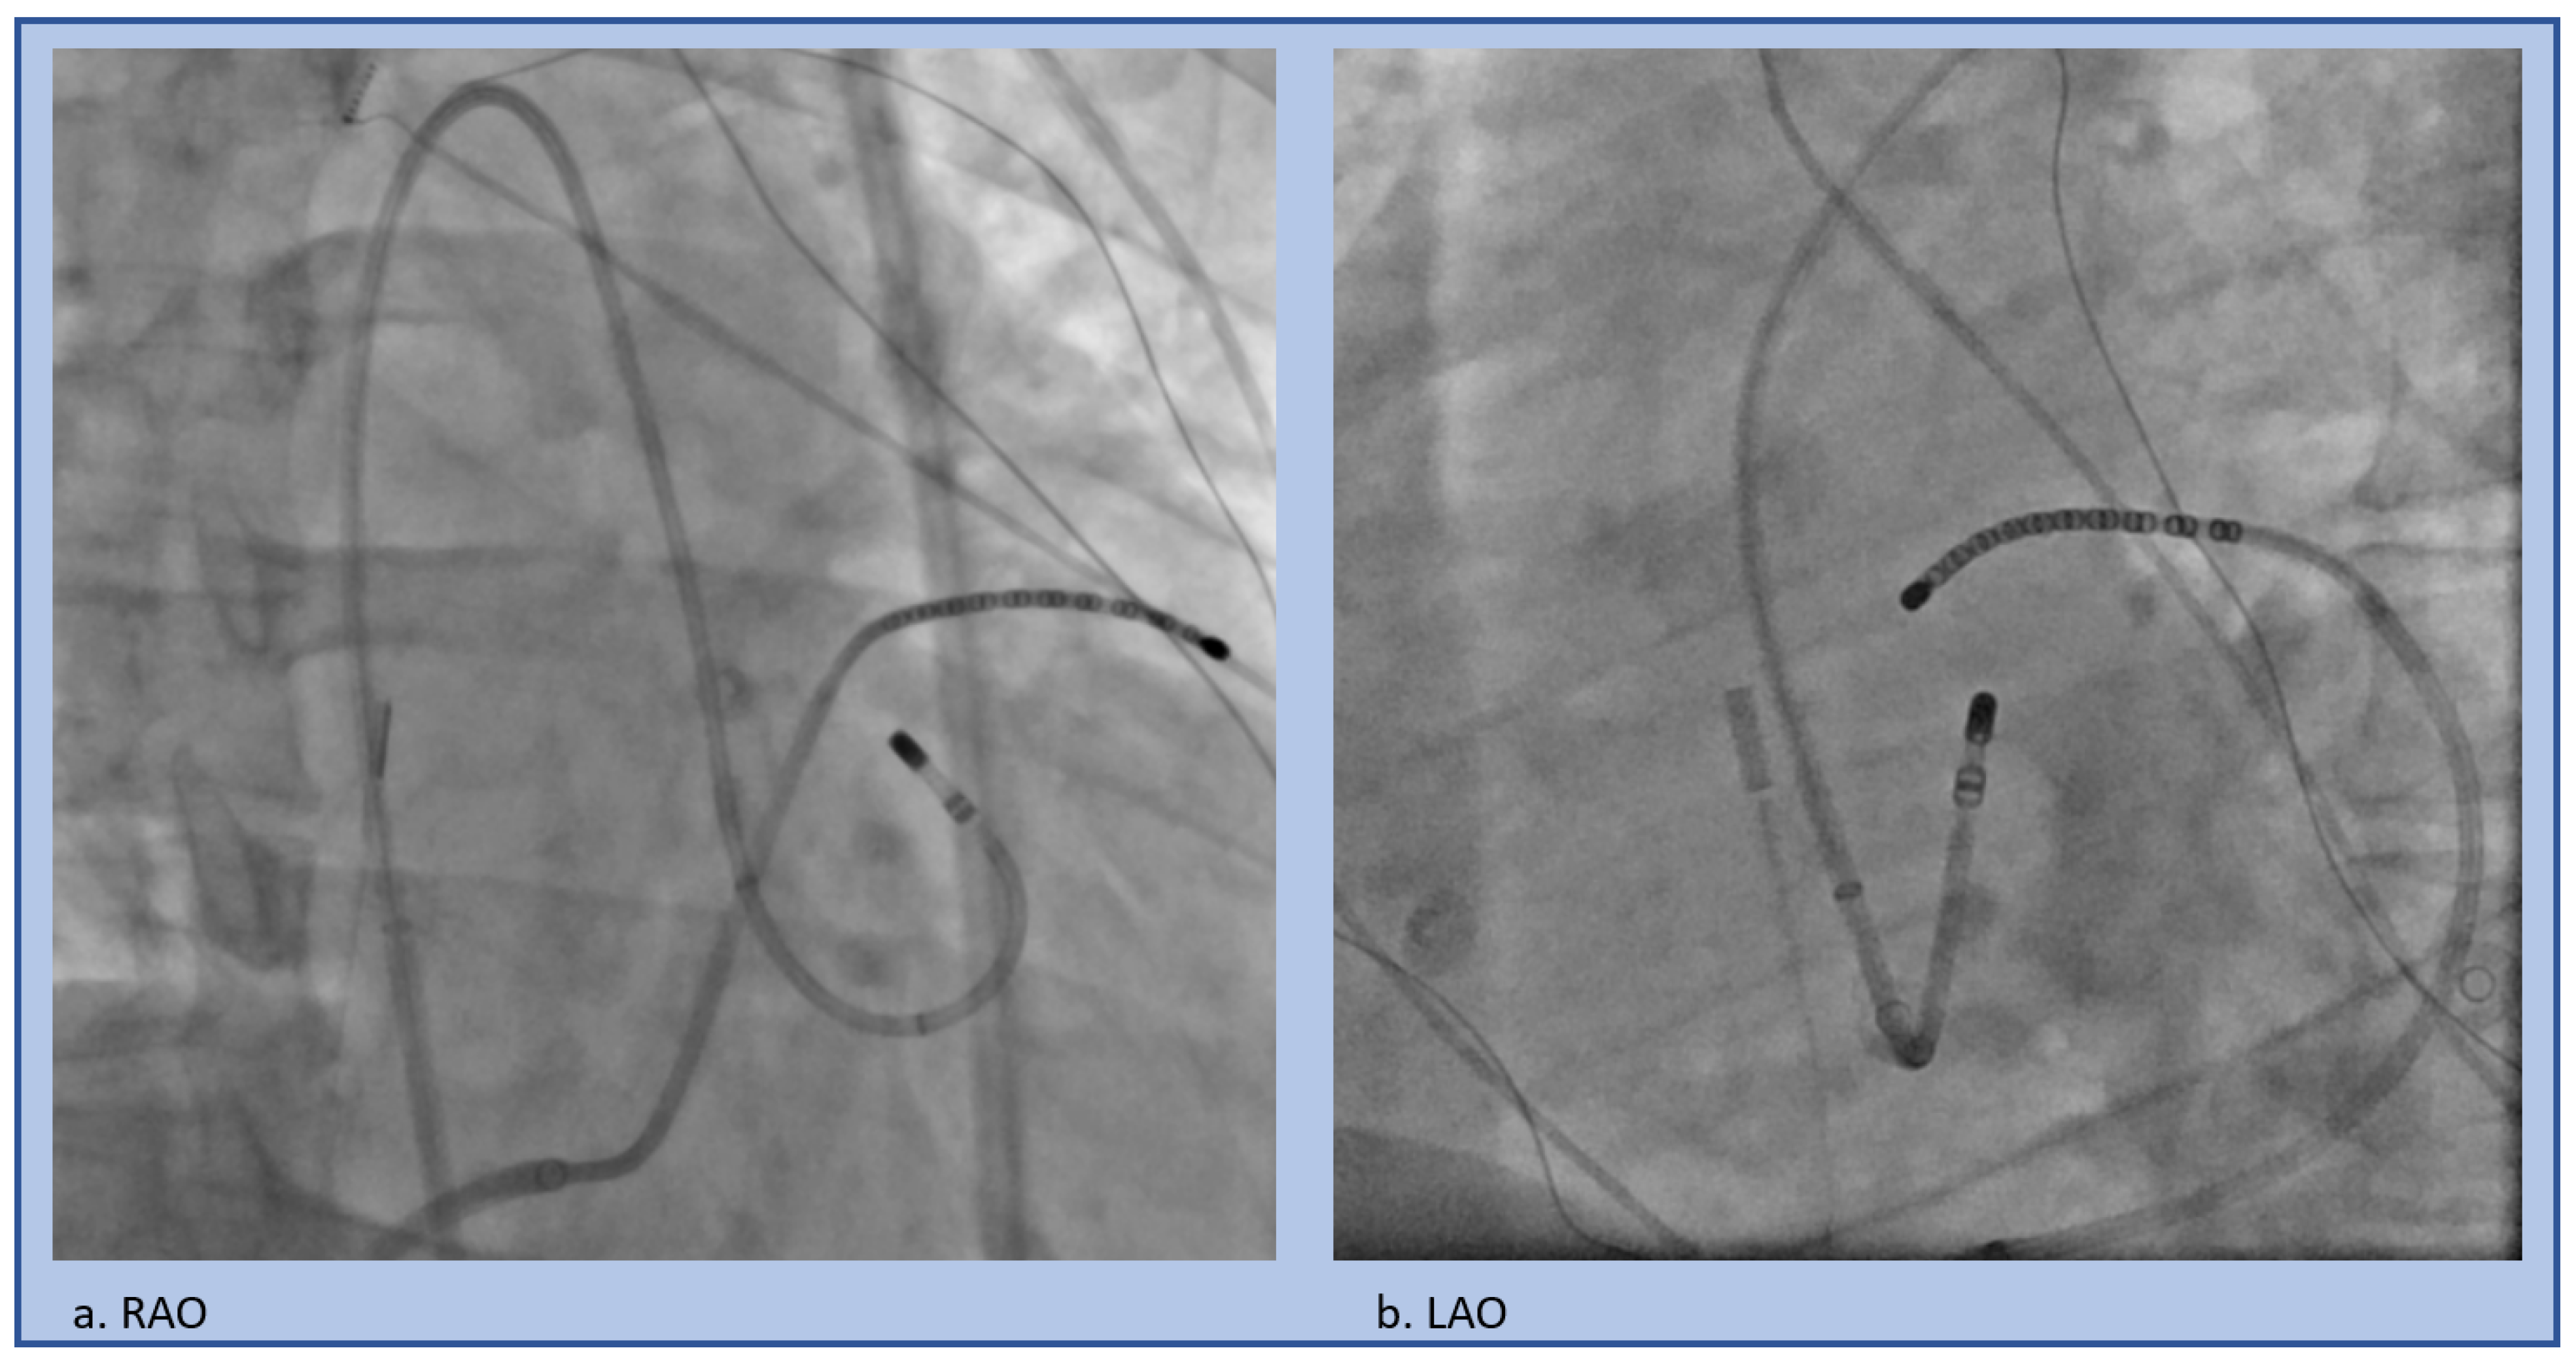

| Moderator Band VT Ablation Tips |

|---|

|